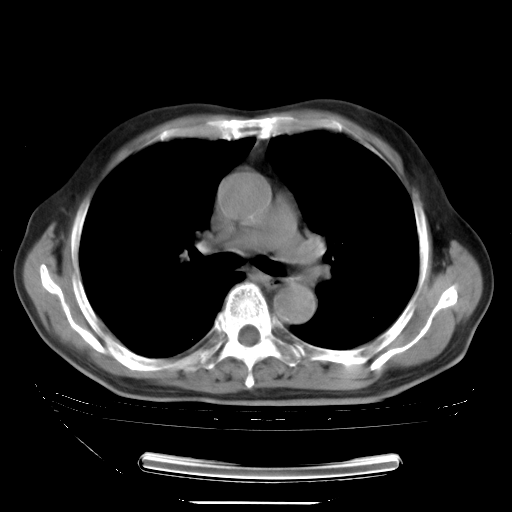

胸腹部CT,诊断意见:左上肺叶钙化灶、左侧胸膜局限性增厚并钙化、胆囊炎。描述部分肺组织呈磨玻璃样改变。